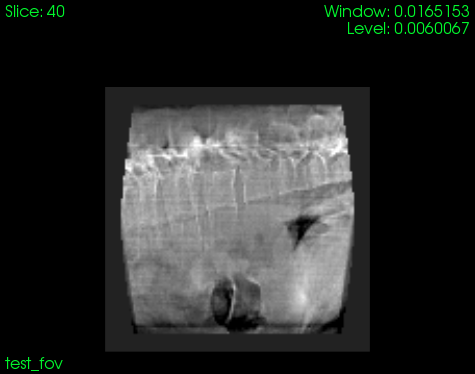

I have tried to reconstruct your data-set using your geometry file and

your projections provided in your DropBox. Considering the number of

projections (292) and the limited angle view (193.1 degrees), I would

say that the results (see attached pictures) are not that bad. Note that

your reconstructed data-set will present truncation due to the truncated

projections that are being used. Therefore you should add a padded value

in order to correct this effect.

rtkfdk -p . -r Cropped_minuslogprojections.mhd -g geometry.xml -o

test_hann.mha --dimension 128 --spacing 2 --pad 1.2

// mask fov

rtkfieldofview -p projections/. -r im1_.*.mhd -g geometry.xml -o

test_fov.mha --reconstruction test_hann.mha